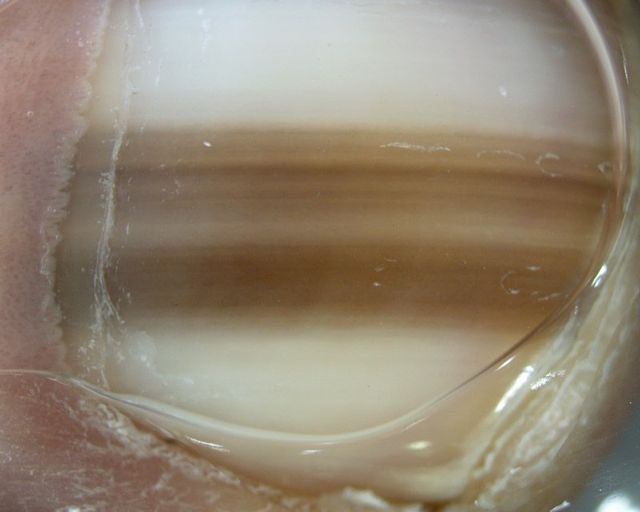

Nail pigmentation is most commonly due to exogenous staining of the nail plate. In this case the proximal margin of the pigmentation follows the shape of the proximal nail fold. Exogenous nail pigmentation is most commonly due to occupational exposures or nail cosmetics. Nail pigmentation due to endogenous causes is rare. The proximal margin of the pigmentation follows the shape of the lunula . Possible causes include drugs, argyria, hemochromatosis, alkaptonuria, and Wilson disease